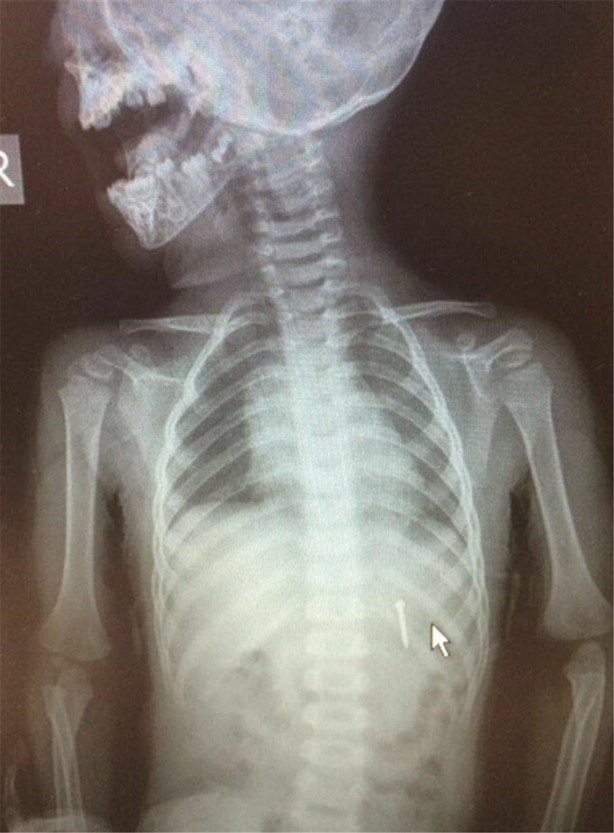

İzmir Tepecik Eğitim ve Araştırma Hastanesi Çocuk Gastroenteroloji Bölümü'nün, yabancı cisim yutan çocukların nefes ve borusu ile midelerinden çıkarttığı, anahtarlık, madeni para, saat pili, ataç, çengelli iğne ve çivi gibi objeler görenleri hayrete düşürdü.

Bu objelerden en tehlikelisinin piller olduğuna dikkat çeken Doç.Dr. Maşallah Baran, "Piller kimyasal mekanizmayla mukozayı yakıyor, özellikle yemek borusu çok duyarlı pillere, hele ki yeni takılmış bir pilse saatler içinde şahit olduğum bir kaç vaka var, yemek borusunu kömür haline getirebiliyor" dedi.